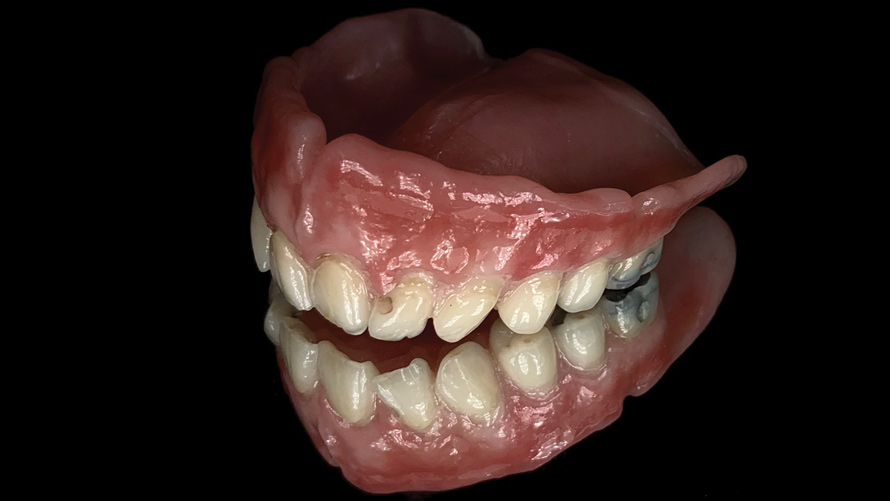

(16.) Photograph of failing implant prosthetics that may require specialty care taken with a smartphone and an EALS device.

Figure 16

(17.) Photograph of failing implant prosthetics that may require specialty care taken with a smartphone and an EALS device.

Figure 17